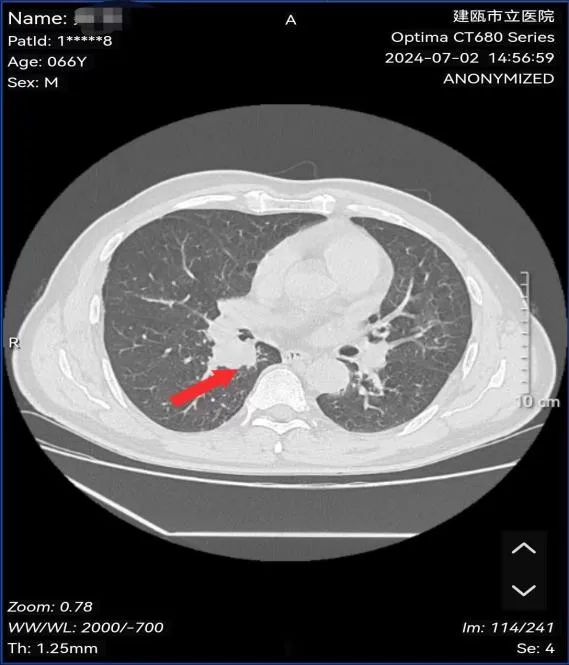

魏先生,男性,66岁,有长期吸烟史20余年,因反复咳嗽数月求诊我院,经肺部CT、支气管镜等检查确诊小细胞肺癌。经肺癌多学科诊疗小组专家会诊:建议完善骨ECT、脑部MRI检查后明确分期为:局限期小细胞肺癌,建议行同步放化疗治疗。

图为:治疗前病灶影像及病理结果